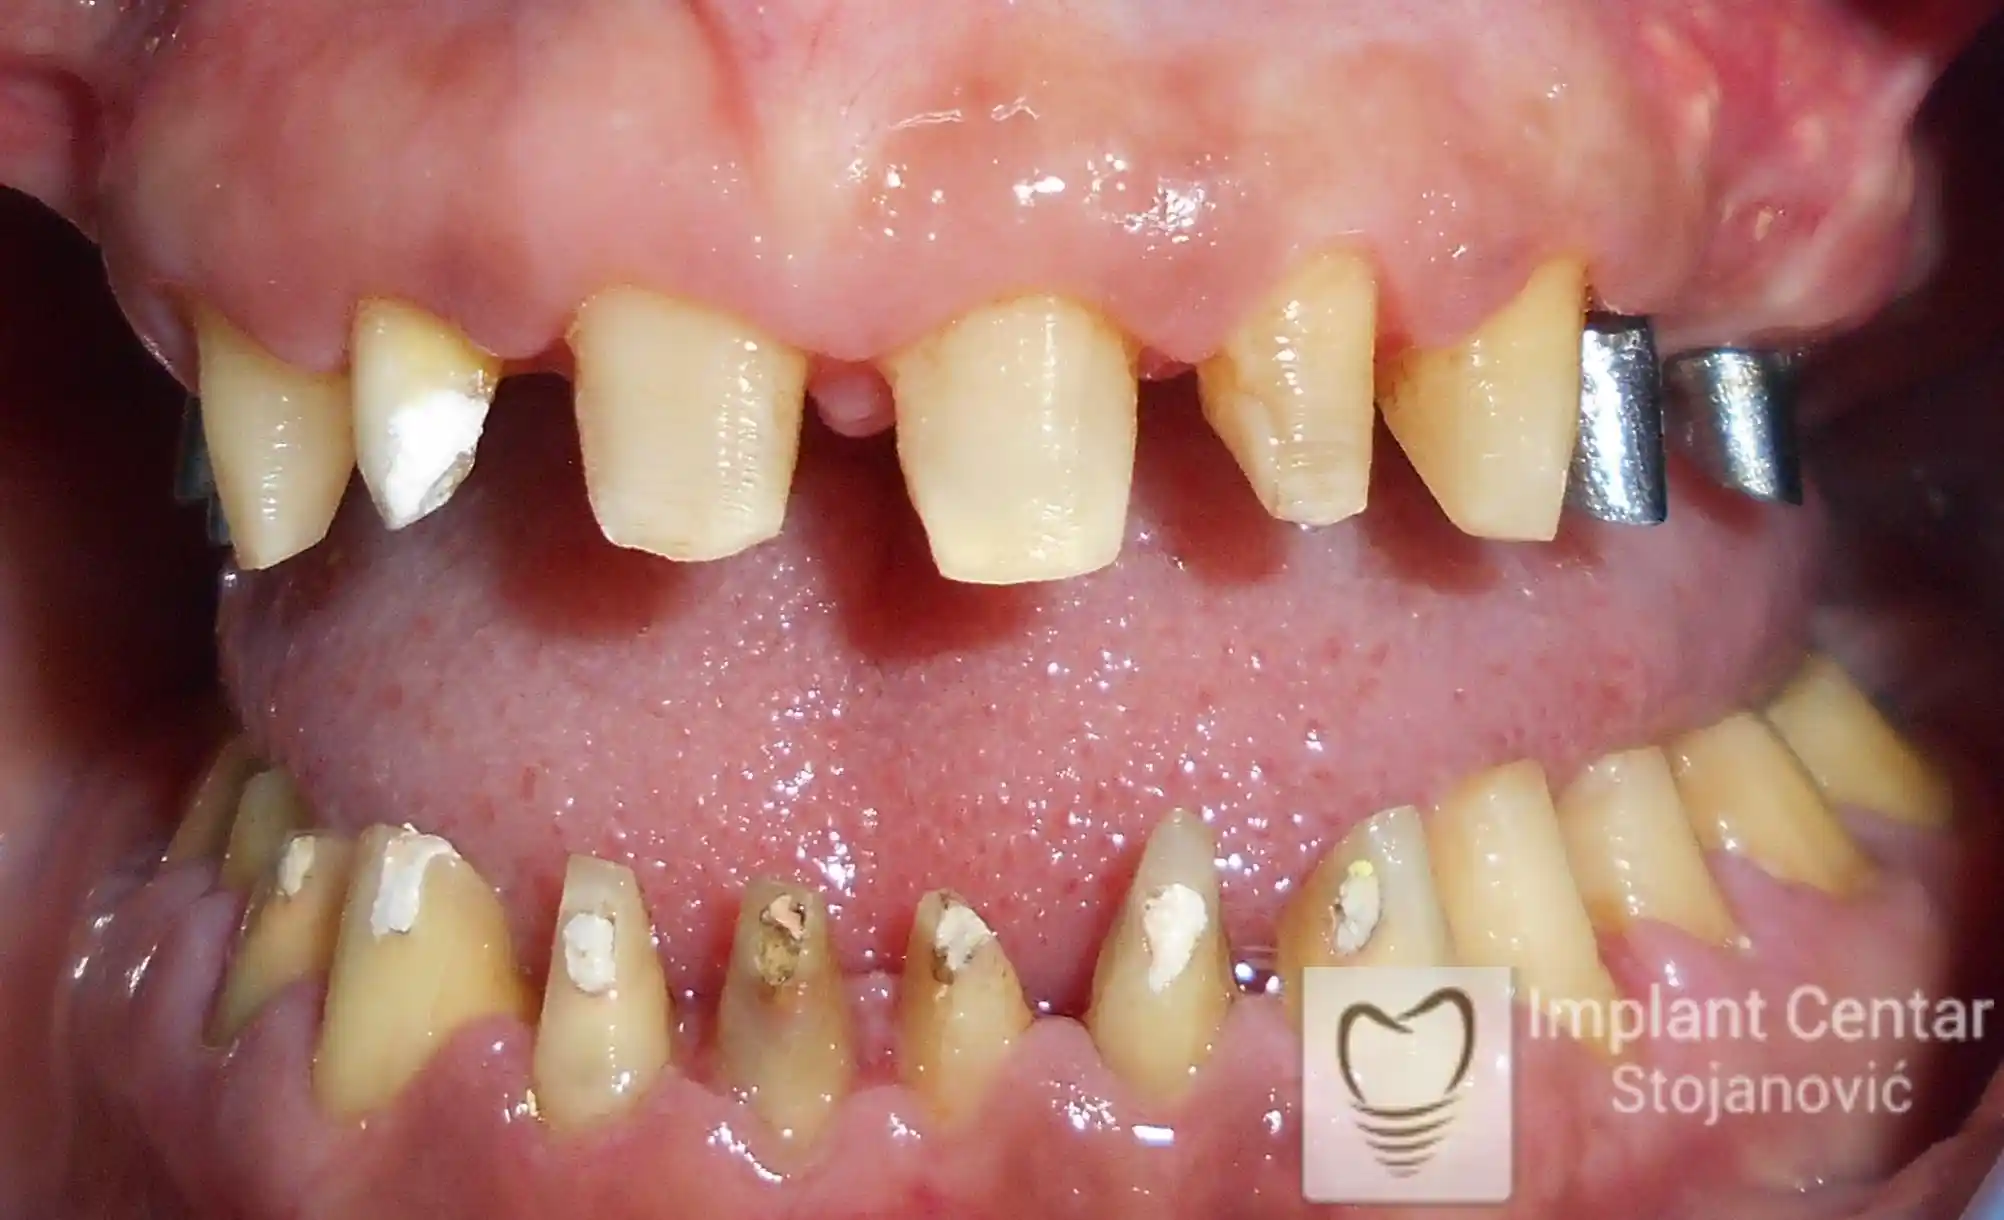

Na slici 1. slici 2. vidi se početno stanje — pacijent je imao prirodne zube, ali samo izradom novih mostova nije bilo moguće postići normalan odnos gornjih i donjih zuba (eugnatan zagrižaj).

Zbog toga je plan terapije uključivao vađenje svih preostalih zuba i ugradnju implantata u gornjoj i donjoj vilici. U gornjoj vilici postavljena su i dva tuberopterigoidna implantata, kao zamena za sinus lift proceduru, što se može videti na ortopan snimku nurađenom odmah nakon ugradnje (slika 3).

Već tri dana nakon operacije, pacijent je zbrinut fiksnim privremenim zubima na implantatima, čime je odmah povraćena funkcija i estetika osmeha.

Nakon završetka perioda integracije implantata, izrađeni su cirkonijum-keramički mostovi u gornjoj i donjoj vilici (slika 6.).